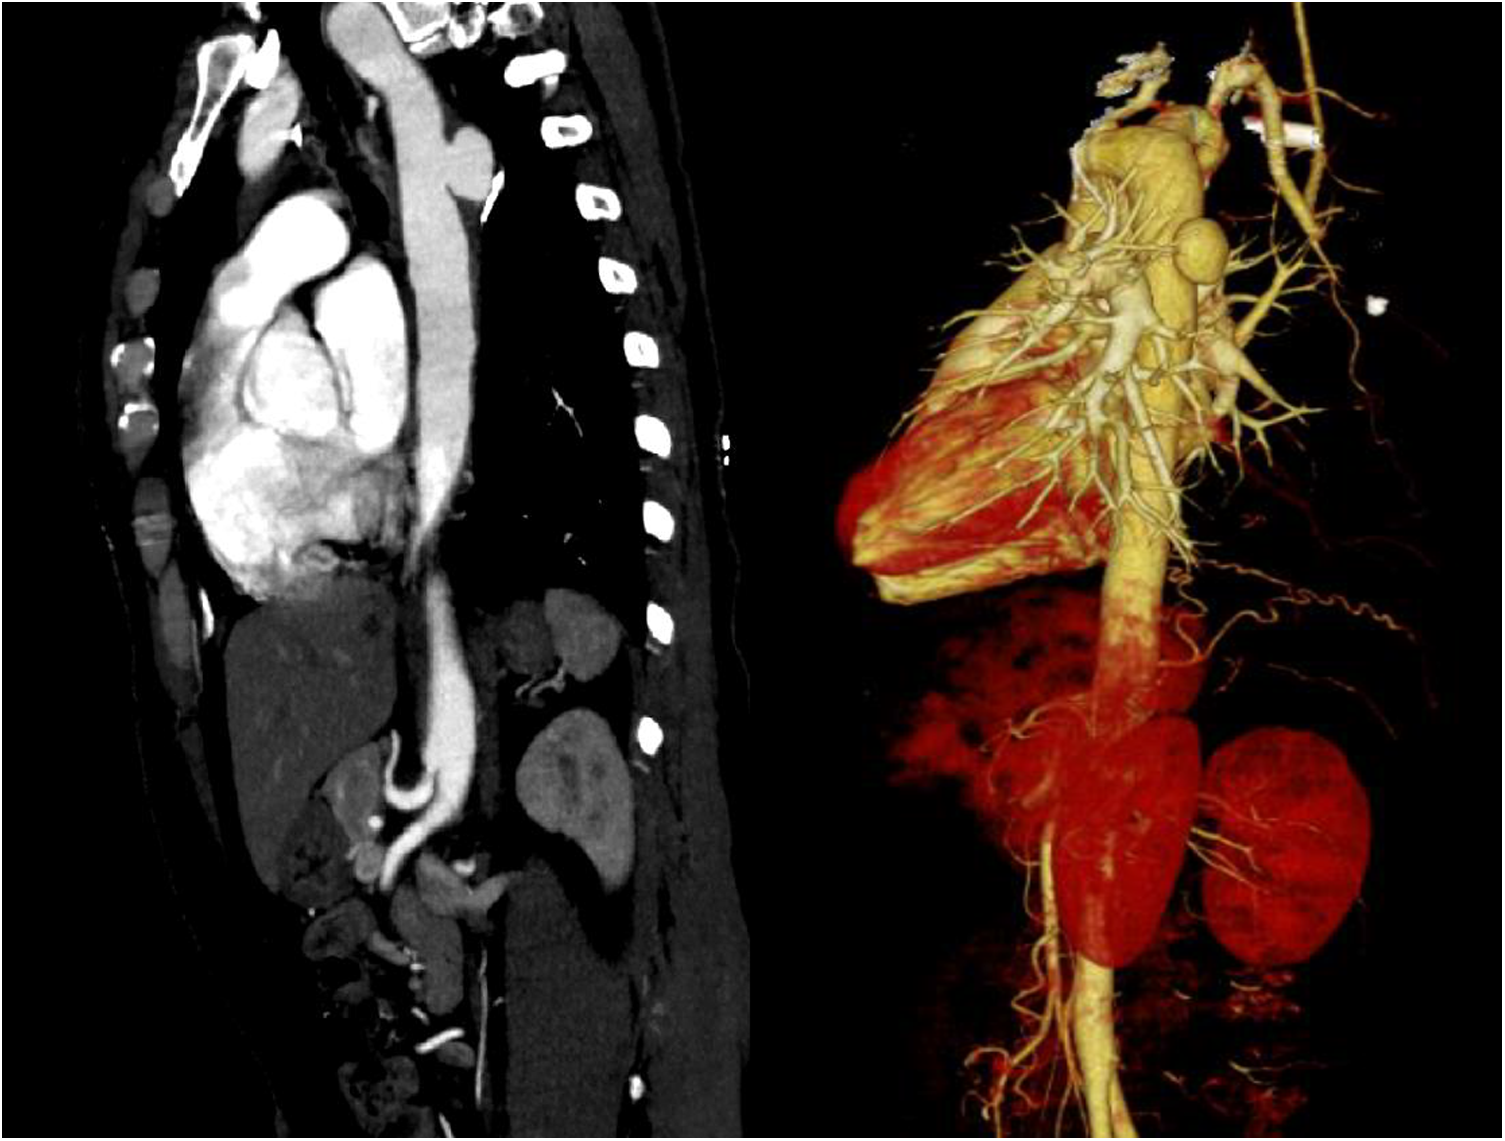

A 43-year-old female patient was admitted to the hospital due to recurrent chest and back pain for more than a month. CTA report indicated: aortic double arch malformation with dissection aneurysm in the descending aorta (Figure 1), right common carotid artery and right subclavian artery were originated from dominant right aortic arch, left subclavian artery and left common carotid artery were originated from left non-dominant left aortic arch (Figure 2).

Figure 1. CTA indicated that aortic double arch malformation with suspected development of dissection in the descending aorta.

Figure 2. Right common carotid artery (RCCA) and right subclavian artery (RSCA) were originated from dominant right aortic arch, left subclavian artery (LSCA) and left common carotid artery (LCCA) were originated from left non-dominant aortic arch.